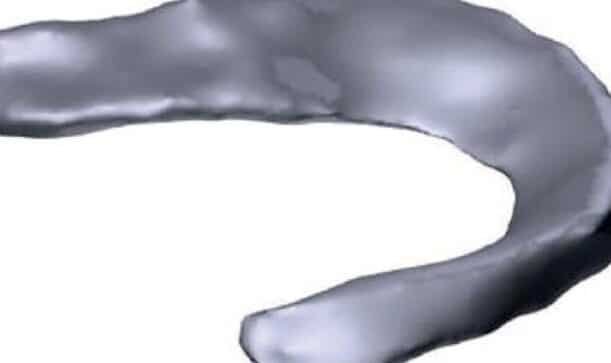

La bioimpresión de meniscos para lesiones de rodilla está revolucionando el campo de la medicina regenerativa, ofreciendo...